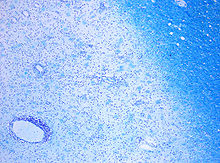

Demyelination by MS. The CD68 colored tissue shows several macrophages in the area of the lesion. Original scale 1:100

Demyelination in MS. On Klüver-Barrera myelin staining, decoloration in the area of the lesion can be appreciated (Original scale 1:100).